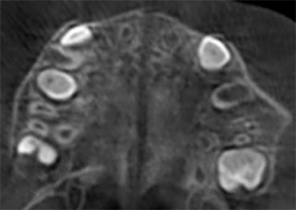

Avant le traitement d’expansion avec les appareils d’expansion palatine Invisalign

Après le traitement d’expansion avec les appareils d’expansion palatine Invisalign

Après le traitement Invisalign First